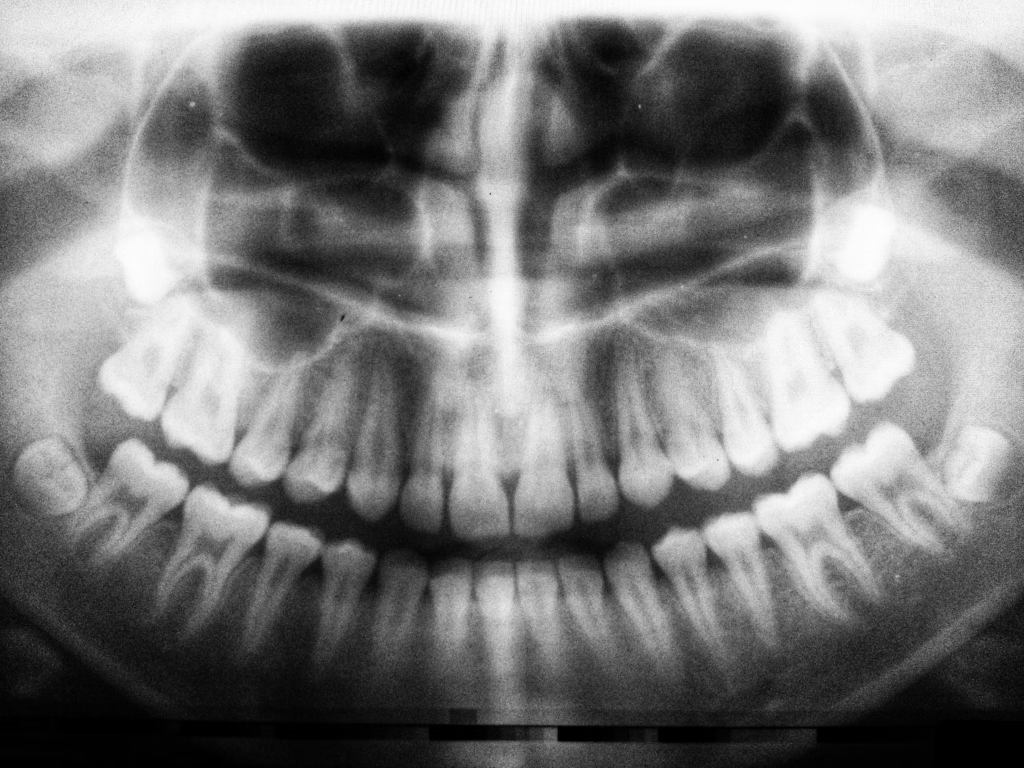

While dental pathology is often benign, it is important to be vigilant for signs that could indicate oral cancer, a potentially life-threatening condition. Early detection improves prognosis significantly.

Dentists play a critical role in screening for oral cancer during routine examinations by thoroughly inspecting the oral cavity and palpating soft tissues. Any suspicious lesions or abnormalities warrant prompt referral to a specialist for biopsy and further management.